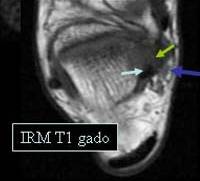

In IRM, exceptional indicat in aceasta patologie, arata un aspect

similar: cu doua semne suplimentare nevizualizate ecografic : participarea

ligamentului grasos infra patelar al lui HOFFA si o afectare

inflamatorie a medulairei osoase la nivelul patelei